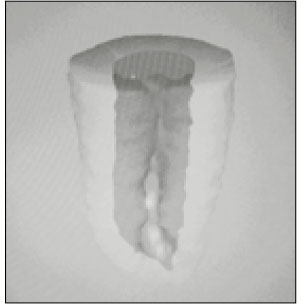

30 mandibular molars with C-shaped root were selected. Six photo images from occlusal, apical, mesial, distal, buccal, lingual directions and radiographic view were taken as preoperative ones to compare them with 3-D image. After crown reduction to the level of 1-2mm over pulpal floor was performed, teeth were stored in 5.25% sodium hypochlorite solution for the removal of pulp tissue and debris. They were cleaned under running water, allowed to bench dry and embedded in a self-curing resin. This resin block was serially ground with a microtome (Accutom-50, Struers, Denmark) and the image of each level was recorded by digital camera (FinePix S1-pro, Fuji Co., Japan). The thickness of each section was 0.25mm. Photographs of serial sections through all root canal were digitized using Adobe Photoshop 5.0 and then minimum thickness of open and closed sites were measured (open site is the surface containing occluso-apical groove : closed site is oppsite). After dizitization using 3-D Doctor (Able software Corp, USA), 3D reconstruction of the outer surface of tooth and the inner surface of pulp space was made. Canal classsification of C-shaped roots was performed from this 3-D reconstructed image.

Conclusively, 3D reconstruction method could make the exact configurations of C-shape root possible to be visualized and analyzed from multi-directions. Data from minimum thickness recommend cleaning and shaping be more carefully done on dangerous mid portion.